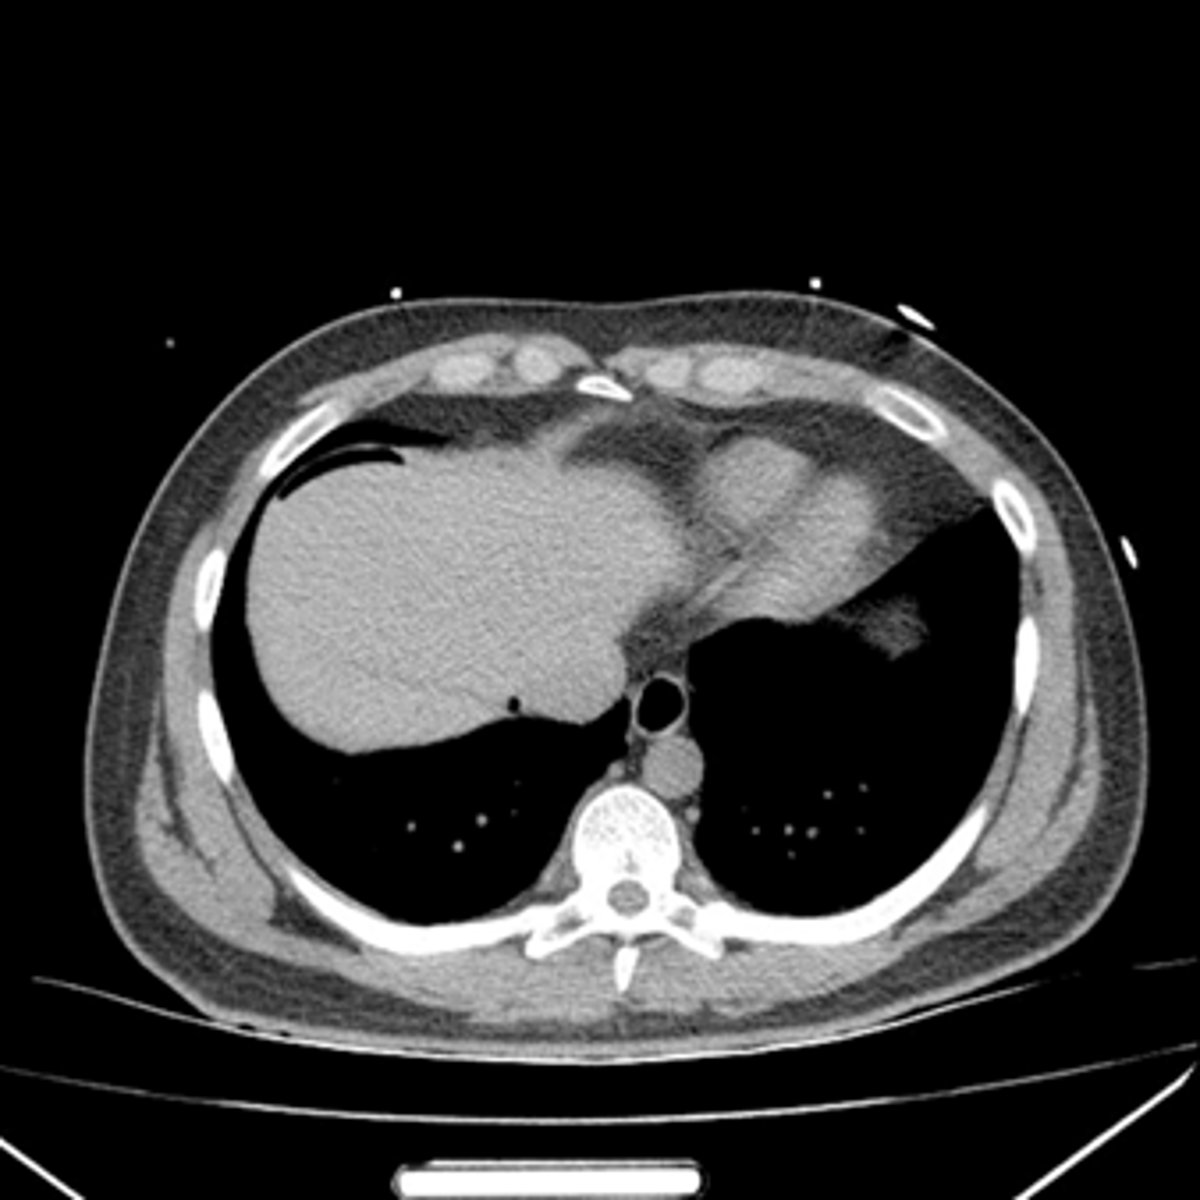

Free air CT